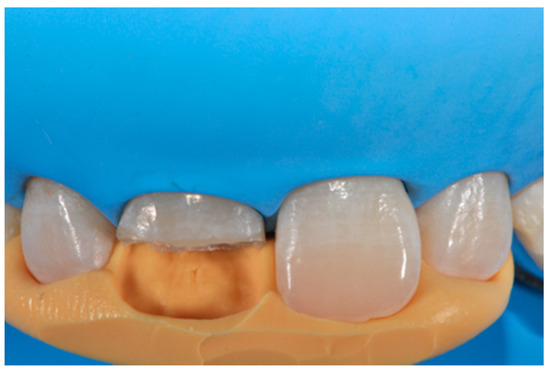

A healthy 38-year-old man referred to the dental office for the esthetic rehabilitation of left central maxillary incisor (Figure 41). Shade was selected as described in previous cases, using the button-try technique [14]. Isolation, preparation (Figure 42) and adhesive procedures were performed (Tokuyama Bond Force, Tokuyama Dental, Osaka, Japan). and Class III was restored on right central incisor (Asteria, A2B, Tokuyama Dental, Osaka, Japan). Frame was then completed on #2.1 (Figure 43) with the use of posterior sectional matrices using translucent and body material (Asteria, NE, A2B Tokuyama Dental, Osaka, Japan). After removing excesses both from the incisal margin and from the interproximal portion (Figure 44) silane and adhesive was applied strictly following the procedure described in Section 2.1.2. Dentinal body (Asteria, A2B, Tokuyama Dental, Osaka, Japan) was applied to reproduce internal anatomy (Figure 45) and then the external translucent enamel (Figure 46) (Asteria, NE, Tokuyama Dental, Osaka, Japan) was applied. The restoration shows good integration 6-months post-operative (Figure 47).

Figure 43.

The frame completed.

Figure 44.

The frame modified either in the incisal frame and in the interproximal wall.